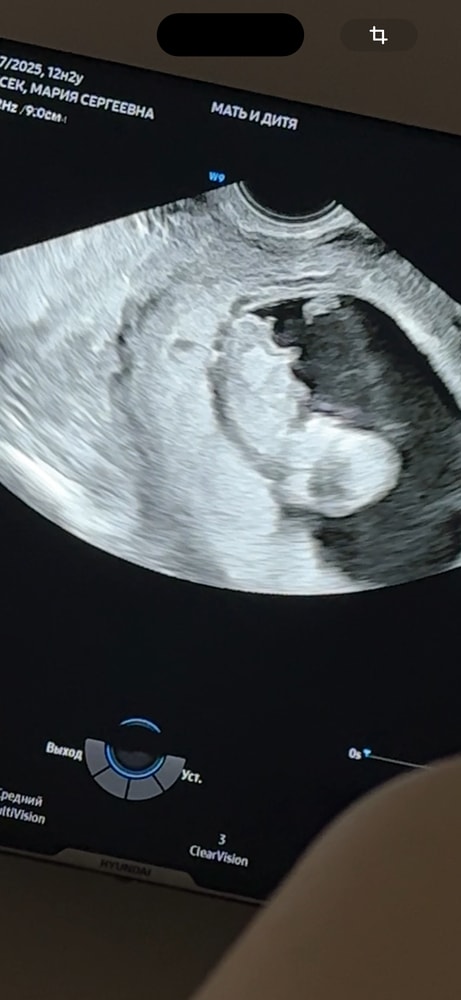

Прикрепляю свои узи, на разных узи разное положение полового бугорка, говорят мальчик, но допустим на второй фотке мне кажется половой бугорок на девочку) что думаете? Читаю разное мнение, что у кого то был прям вверх половой бугорок, а итог девочка и наоборот

сейчас срок по узи 13.2

В 15,3 у нас была уже четко девочка, то есть не половой бугорок, а вполне себе четкие половые признаки, не перепутать. У вас на втором фото ракурс не четко профиль, мне кажется, а чуть повернут, соответственно выводы делать нельзя. По другим фото похож на мальчика, но опять же на таком сроке 1: ошибки явление частое 2: мы ж не врачи) повторите УЗИ недель в 15-16, там уже четко всё видно, половые органы сформированы.